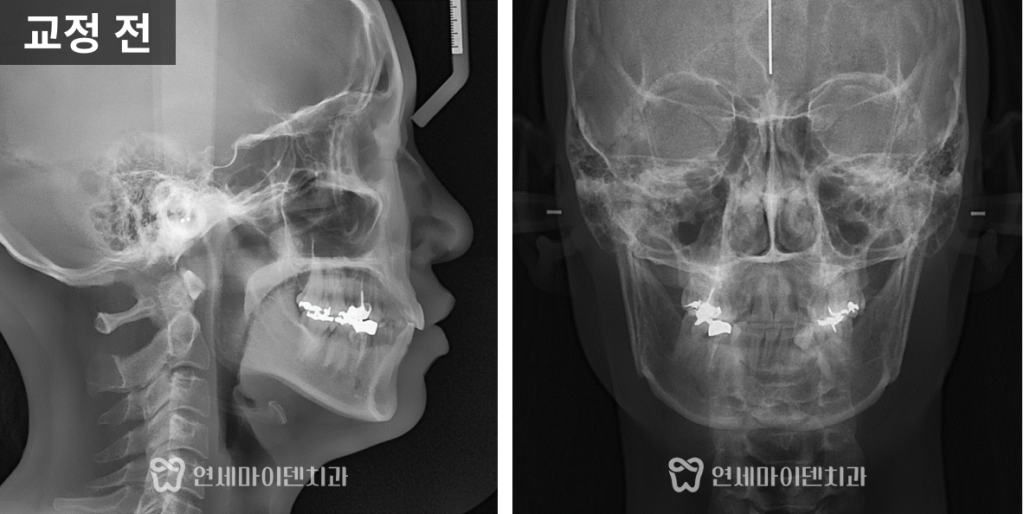

얼굴 전체의 골격적인 이상은 없었지만

수직으로 짧은 얼굴형 때문에

아래 입술이 돌출돼 보이는 인상이 있었습니다.